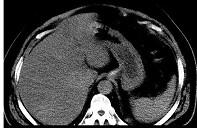

问题 男,32岁,肥胖,常酗酒,肝肋下一横指,肝区轻微压痛,影像表现如图,应诊断为 ( )

选项 A.肝炎 B.肝硬化 C.脂肪肝 D.肝豆状核变性 E.肝含铁血黄素沉着

答案 C